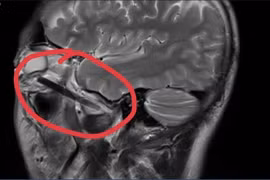

Ca phẫu thuật đặc biệt lúc 2 giờ sáng tại Bệnh viện Đa khoa tỉnh Bình Dương

Bệnh viện Đa khoa tỉnh Bình Dương đã thực hiện thành công ca lấy tạng từ người hiến chết não để chuyển đến các bệnh viện khác.